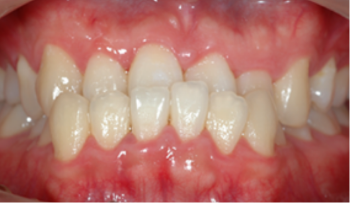

첫 내원(초진)

치아와 안모에 대한 임상검사를 합니다.Orthodontics

치아와 안모에 대한 임상검사를 합니다.